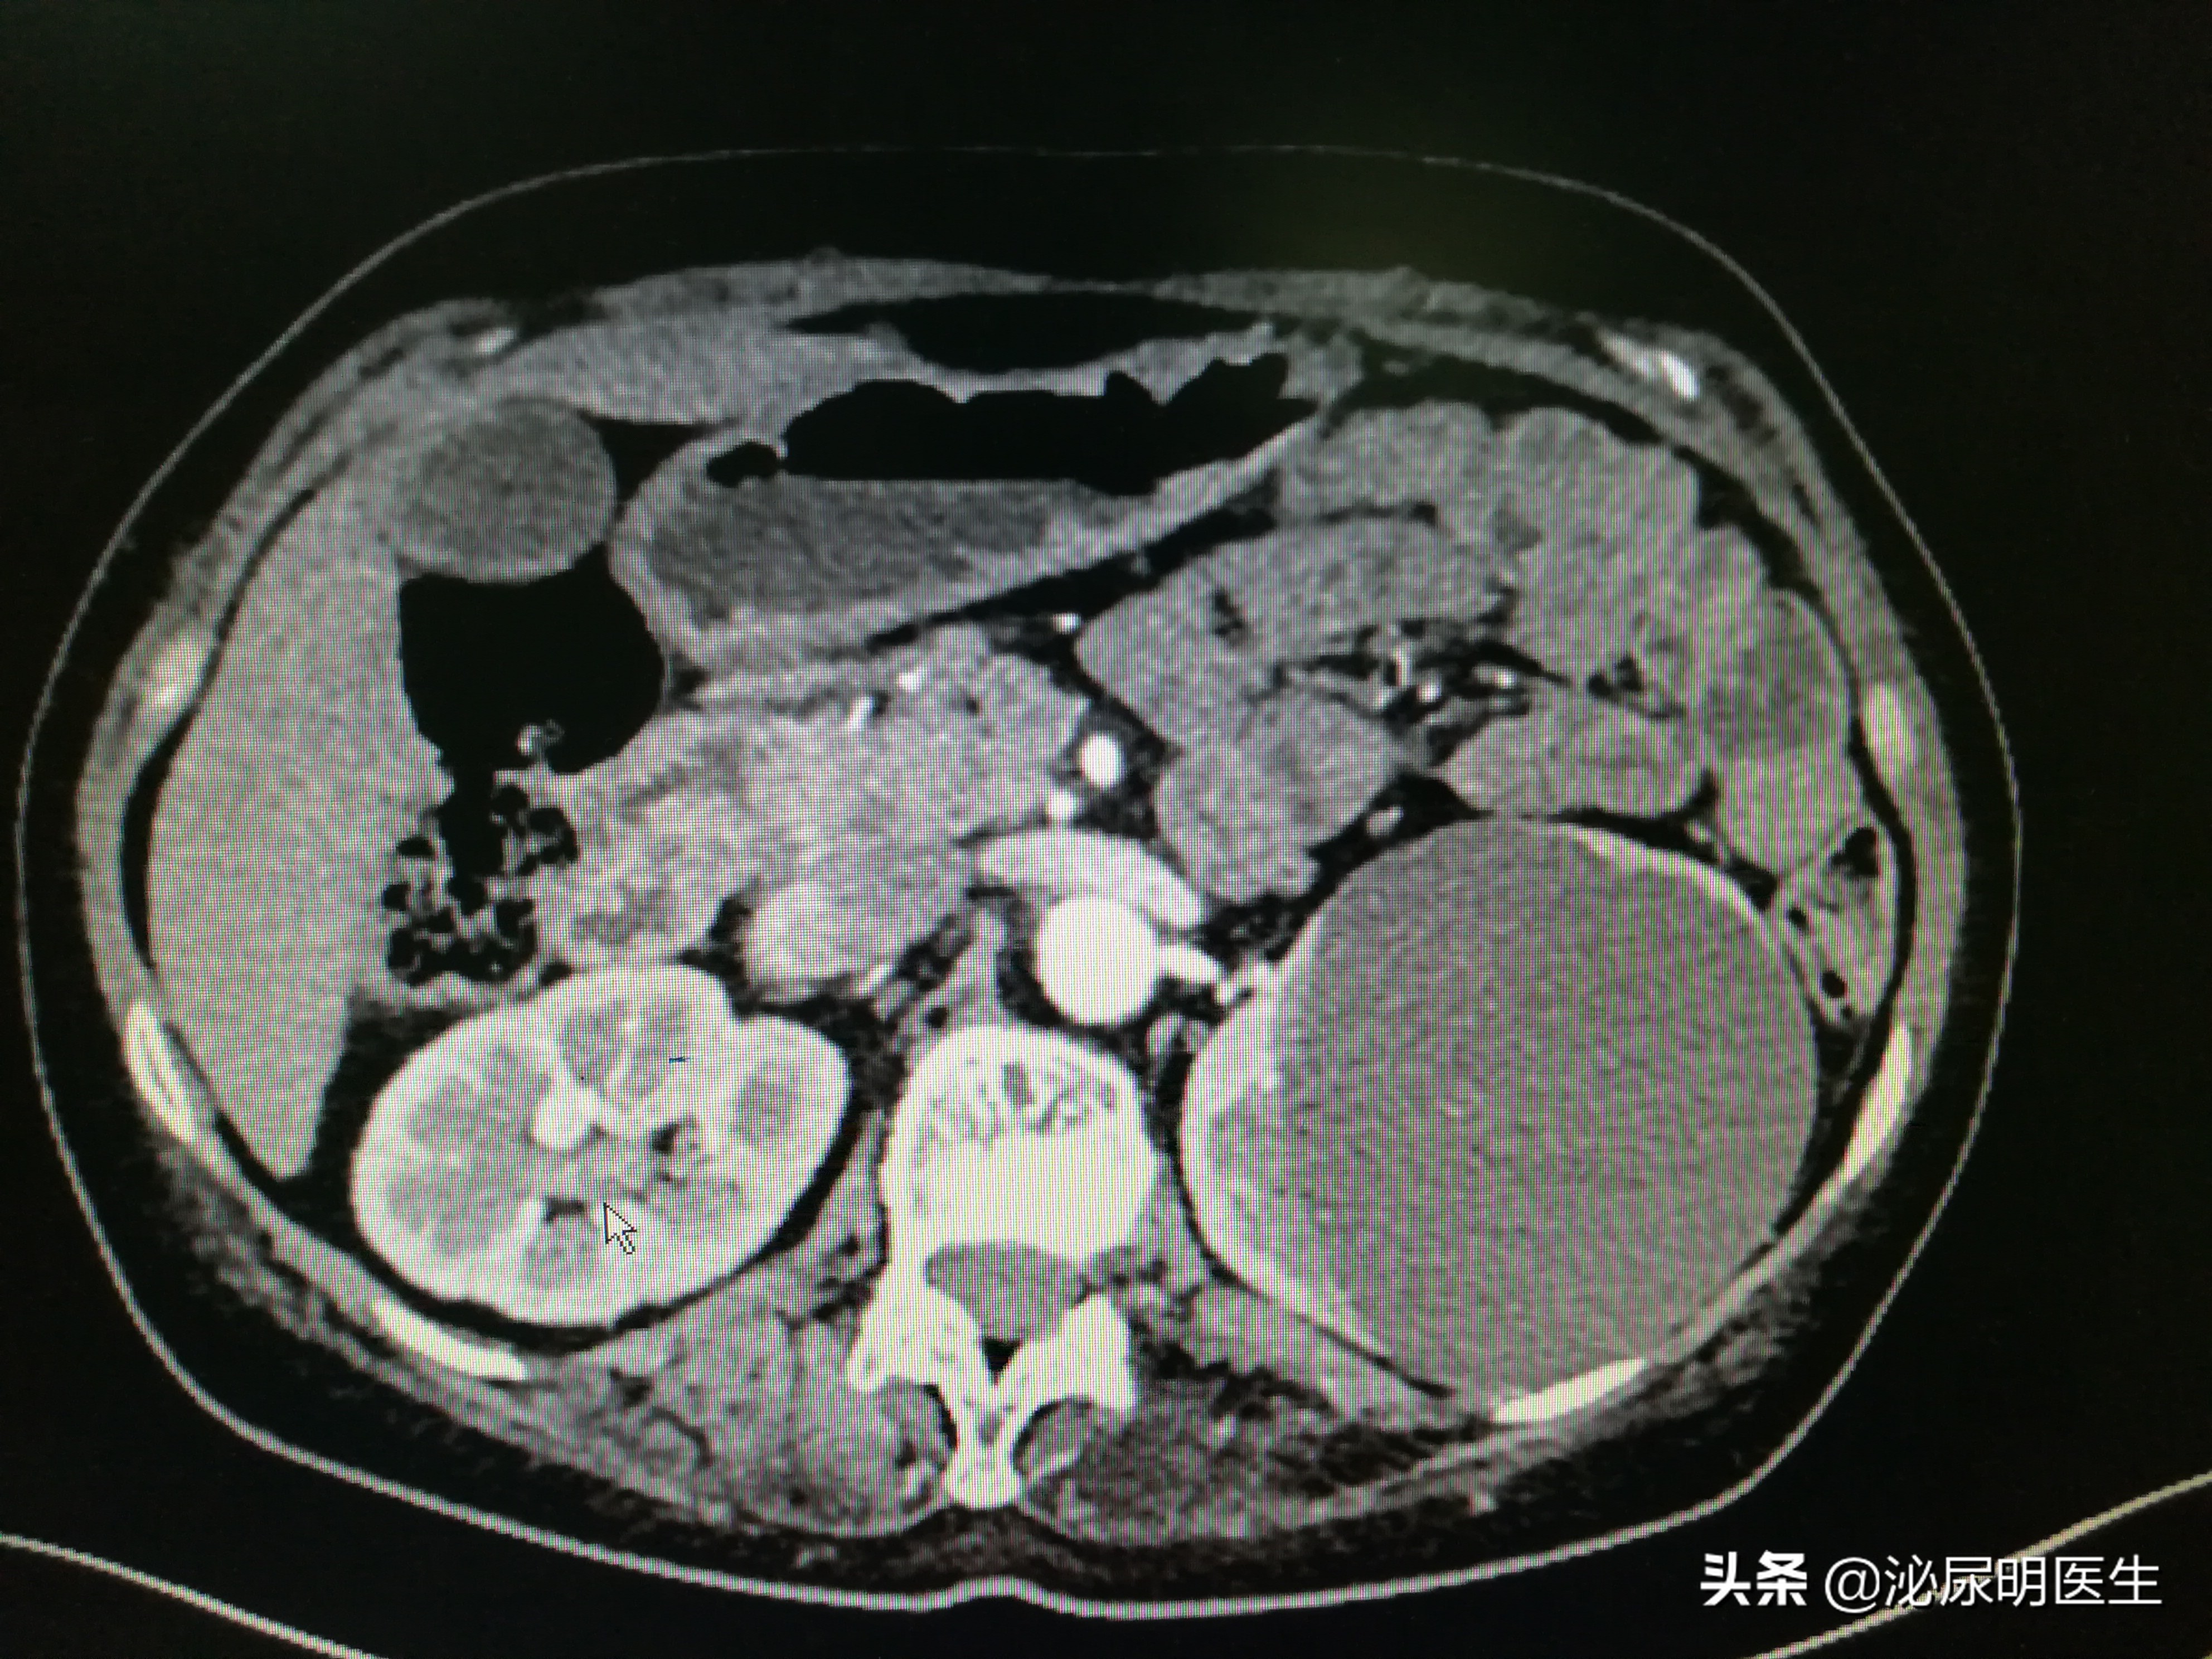

肾囊肿位于左肾上级

肾脏呈受压迫的表现